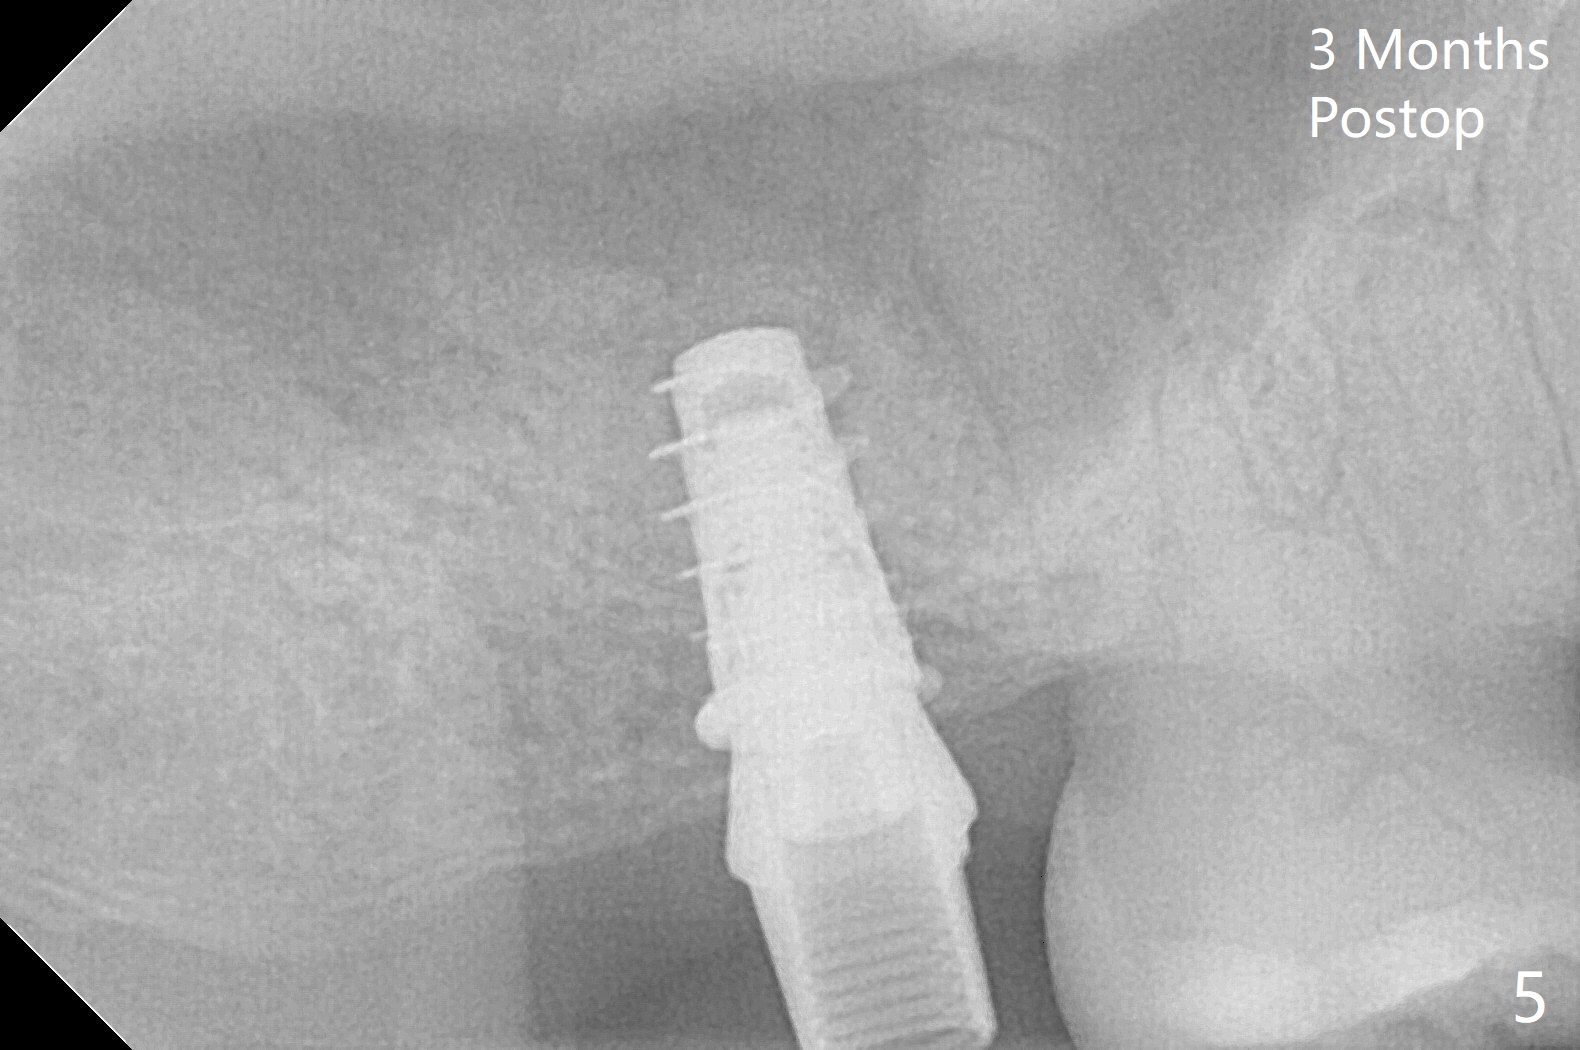

With 4-5 mm remaining bone at #2, the initial osteotomy is 4.0x3.5 mm with regular drills with sharp end. After using 3.6 mm sinus drill with round end for ~ 4 mm in depth, water lifting is conducted smoothly. After use of the same safe drill for ~ 5 mm, water lifting is done. Nose blowing indicates possible sinus membrane perforation. With insertion of collagen plug (PRF is not prepared because of thin vein), mixture of autogenous bone and allograft is lifted with 4x9 mm dummy implant with a guide (Fig.1 G). With placement of more of bone graft, a 4.5x7 mm definitive implant is placed with ~ 25 Ncm (Fig.2). Although bone graft around the implant is limited (Fig.3,4 *), the sinus membrane is lifted (in fact expanded by water) substantially (arrowheads, as compared to preop CT). The healing abutment is dislodged 1 month postop. Before impression, use sensor 1 to take PA to determine whether the abutment contacts the crestal bone or not. Take 5x5 cm CT for sinus membrane thickness. Although the bone graft surrounds the implant 3 months postop, the implant is tender when a 4.5x4(2) mm cemented abutment is being placed (Fig.5). Later a healing screw is placed (Fig.6,7). The sinus membrane has shrunk (arrowheads). Progressive loading is mandatory. The implant is uncovered with a 6x2 mm healing abutment 6.5 months postop (Fig.8). A 5.5x4(2) mm pair abutment is placed and torqued at ~20 Ncm with mild tenderness 7 months postop (Fig.9 BW). A provisional is fabricated for progressive loading because of mild crestal bone loss (*). The abutment is able to be torqued at 35 Ncm 9 months postop. Impression is taken. Return to Upper Molar Immediate Implant Trajectory II 18 Next Case with 3-4 mm Bone Screw Xin Wei, DDS, PhD, MS 1st edition 10/29/2019, last revision 02/23/2021